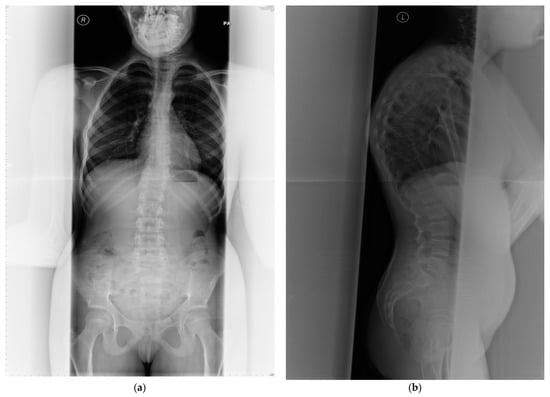

2.1. Skeletal Characteristics of PMM2-CDG

PMM2-CDG is the most prevalent disorder of abnormal glycosylation of N-linked oligosaccharides leading to endocrine abnormalities including dysfunction of IGFBP3 and an acid-labile subunit in the IGF pathway which result in short stature [11]. Growth failure is commonly observed in children with PMM2-CDG [7,12,13,14,15,16,17]. Despite normal serum calcium, phosphate and magnesium concentrations, osteopenia/osteoporosis are frequently demonstrated in this condition since childhood (Table 1) [8,9,10,11,12,13,14]. Skeletal abnormalities are common, although under-diagnosed [17], often leading to kypho/scoliosis, severe spinal cord deformity and vertebral compression fractures [7] (see Figure 2). Regular orthopaedic assessment and intervention are required if scoliosis becomes evident, with cervical spine x-rays in neutral, flexion, and extension to assess for atlantoaxial instability. Fractures are common and appear to heal normally. Skeletal dysplasia is not a typical feature of PMM2-CDG but has been reported before (Table 1 and Table 2). Joint contractures are relatively common and affect patients’ quality of life.

Figure 2.

(a) Anterior posterior view—whole spine x-ray in a 25-year-old female patient affected with PMM2-CDG; bone mineral density is below expected for her age (T score −2.6, z-score −2.6); (b) lateral view; (c) radiological features of her lumbar spine: there is a double mild curve scoliosis and no rotational deformity. All pedicles are visualized. There is impression of slight upper hyperkyphosis and impression of multilevel Schmorl’s nodes.

The effectiveness of supportive management can be evaluated by DEXA scan (Figure 3), a gold standard method for monitoring the progression of bone mineral density decline. The whole spine x-ray (Figure 2) can be used for identification of bone deformities and fractures. QCT however is the sensitive quantitative method used to assess the bone mineral density. Body composition has become increasingly utilized in Inherited Metabolic Disorders field and provides additional information about the bone and muscle involvement.